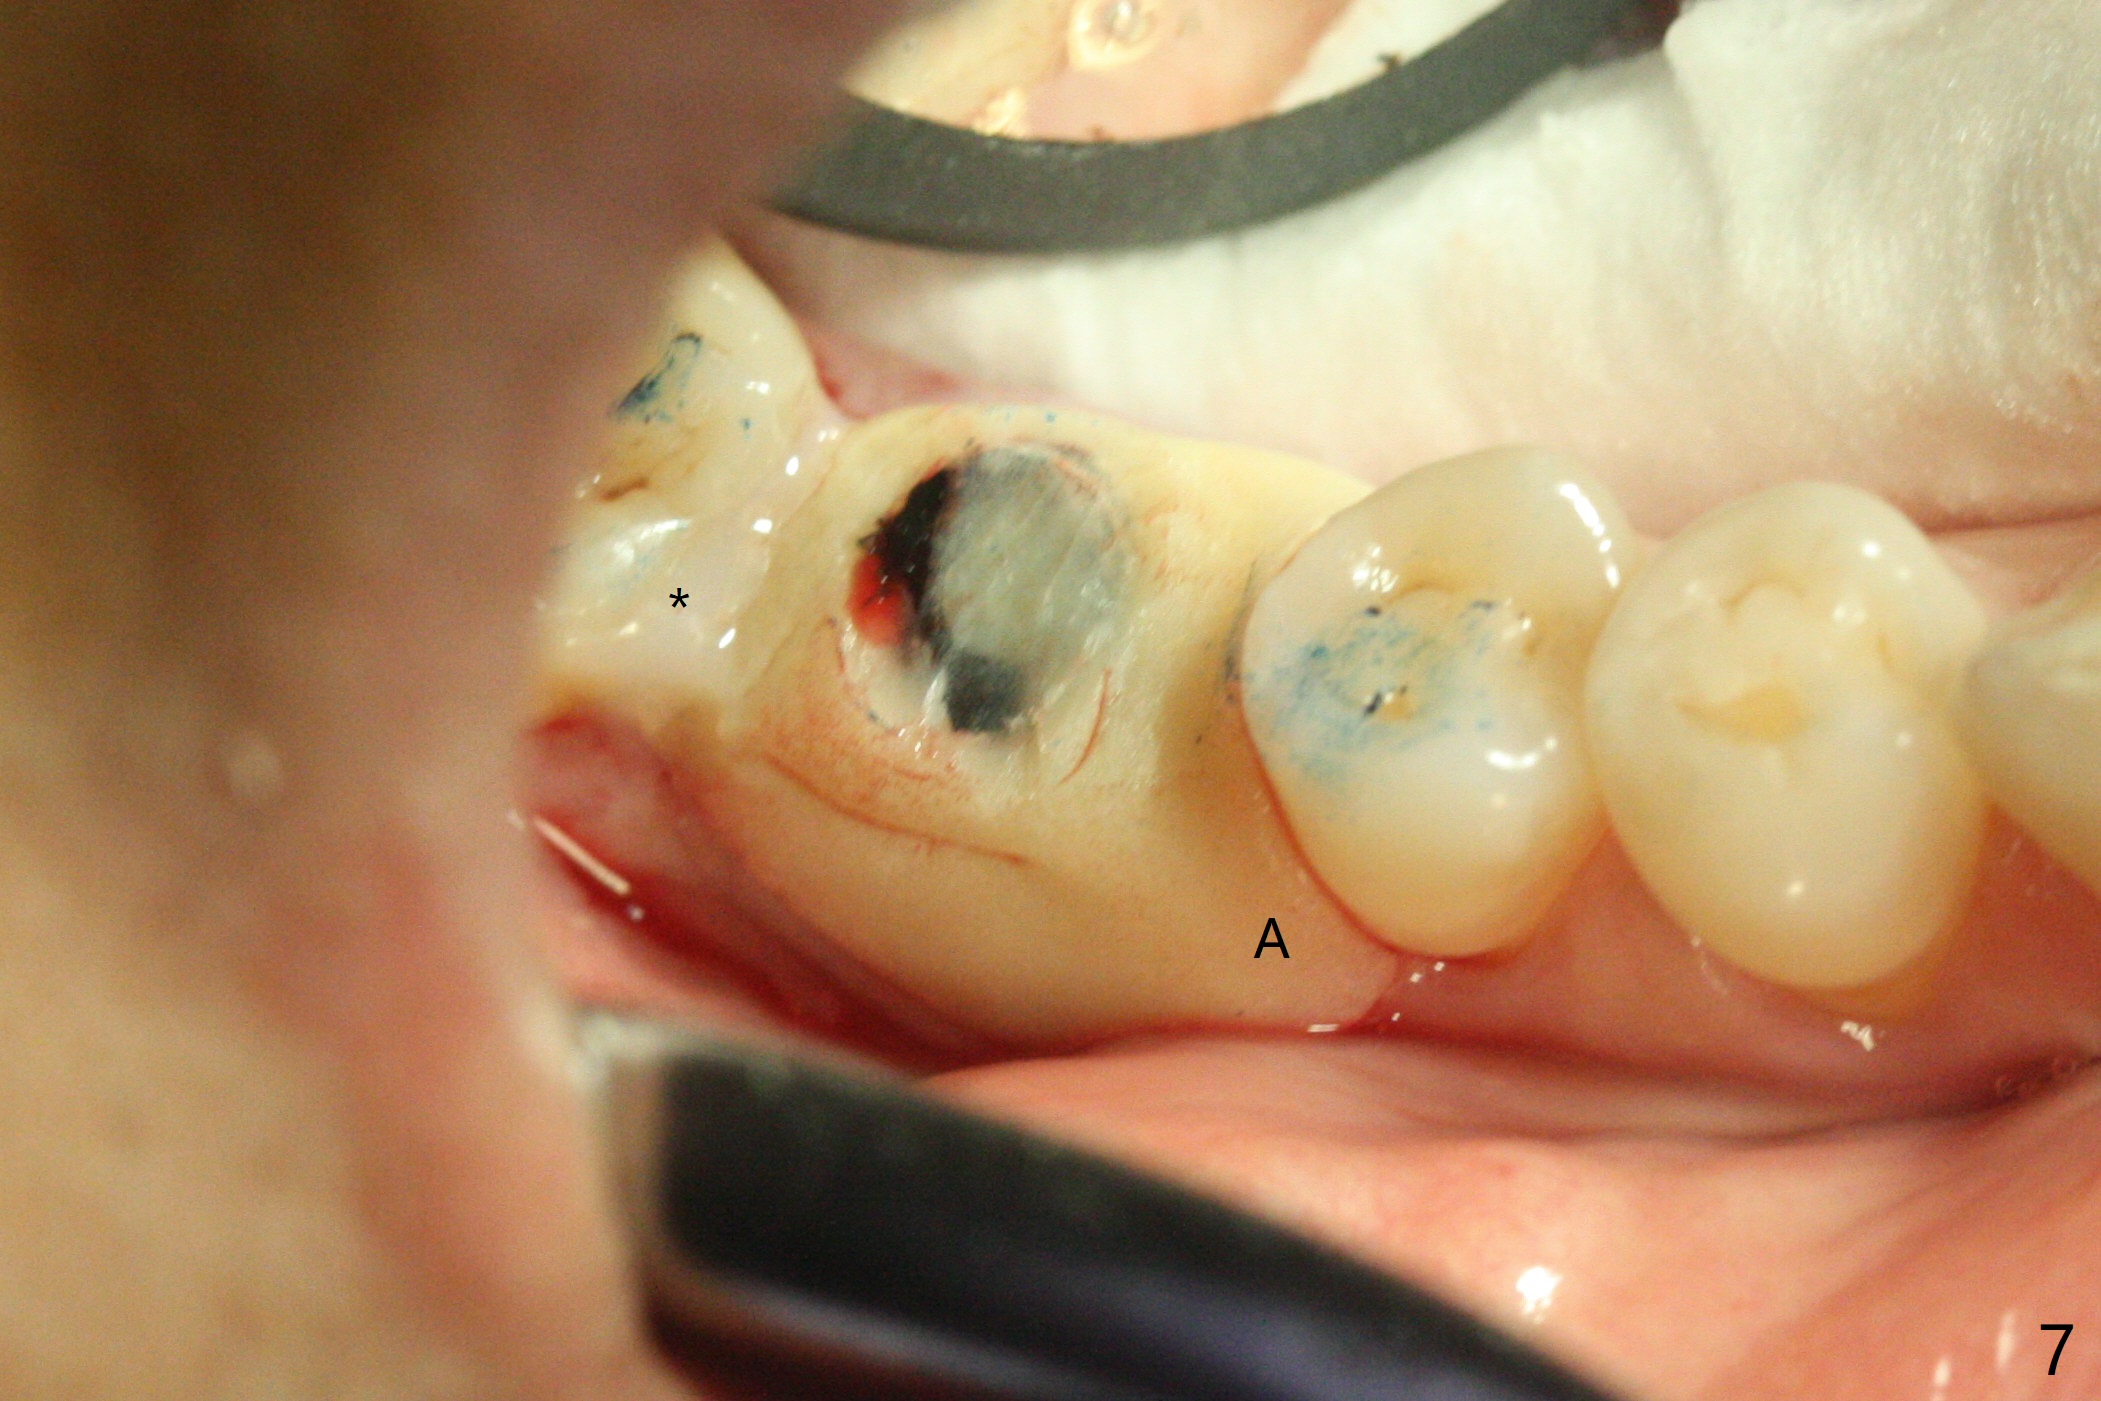

To prevent further postop buccal gingival recession at #30, socket shield is formed with removal of the residual roots (Fig.1,2 *). Osteotomy is initiated in the septum (Fig.2 S, to be flattened with bone trimmer and surgical round bur) and gradually slides slightly into the mesial socket in spite of using surgical guide (Fig.3 *: sleeve). Following 4.5x11.5 mm drill, a 4.5x8 mm Bicon implant is pressed fit; its stability is lightly enhanced with placement of sticky bone in the remaining sockets (Fig.4 *) and around the black plug (Fig.5 P). After removing the coronal portion of the plug to reduce occlusal interference, two pieces of PRF are wrapped around the remaining plug (Fig.6). The main stability of the implant is obtained when setting acrylic (A in Fig.7) is applied into the edentulous space (undercut). After acrylic setting, flowable composite (*) is added distal for further retention. One month postop, the flowable composite is detached. The provisional is sectioned; the black plug is cut. The socket heals with exposure of the mesial socket shield (Fig.8 >). The black healing plug and the mesial socket shield remains exposed 3 months postop (Fig.9). When a 4.5x6.5 mm temporary abutment is placed, the buccal gingiva is blanched and the mesial socket shield is pushed buccal (Fig.10). The implant appears to remain covered by the bone 3 months postop (Fig.11). Cortical bone starts to form crestal 7 months postop (Fig.12 arrowheads, coronavirus). The cortex seems to thicken 8 months postop (Fig.13 *).